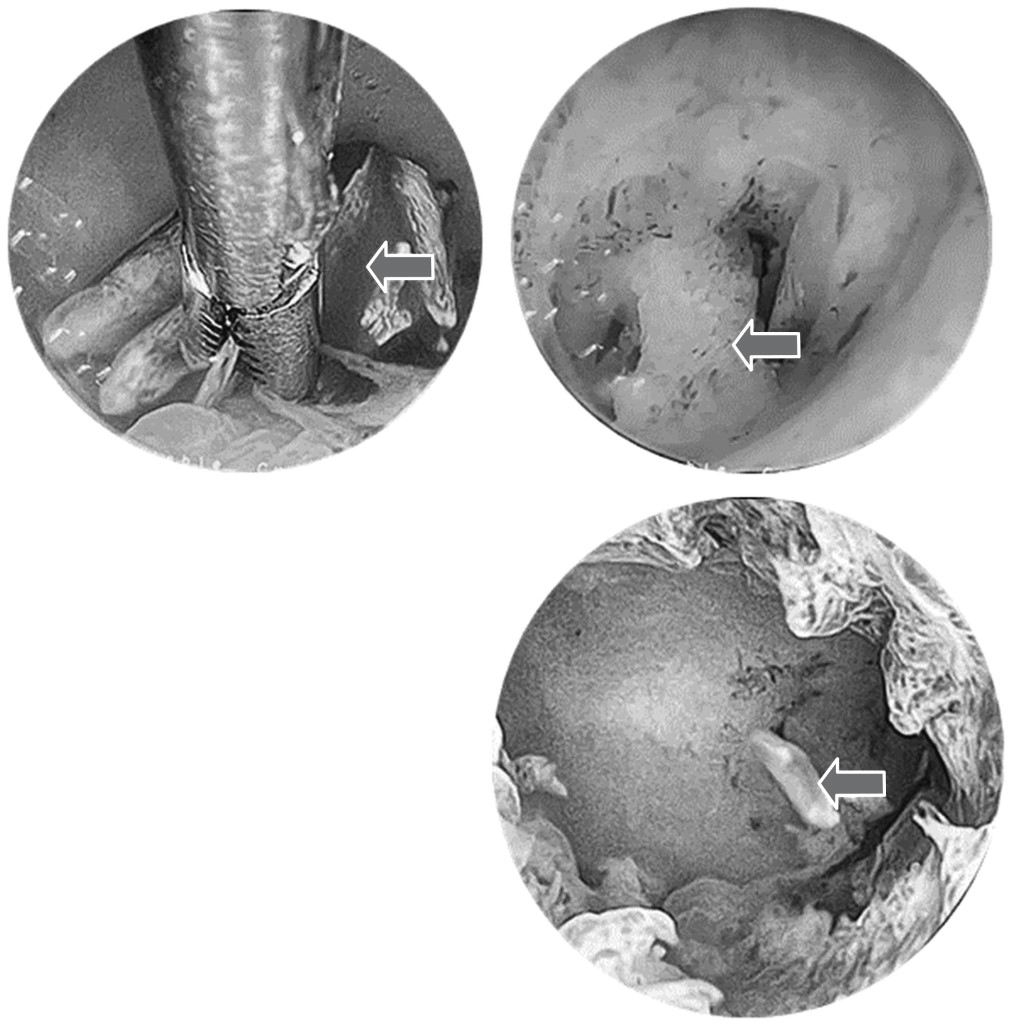

Ante ello, se decidió efectuar una histeroscopia diagnóstica, que dejó ver una cavidad uterina con evidencia de ostiums y recesos libres (Figura 1). No se identificó un DIU, pero se observaron múltiples fragmentos de consistencia dura y color blanquecino de distintas dimensiones (el mayor de 0.5 cm; el menor de 0.2 cm), los cuales fueron extraídos con pinzas histeroscópicas Grasper para dejar limpia la cavidad uterina (Figura 2). El reporte histopatológico registró varios fragmentos de tejido que, en conjunto, midieron 10 × 5 × 5 mm; también se identificaron trabéculas de hueso bien formadas, sin componentes celulares de médula ósea y con diagnóstico de metaplasia ósea.

En el presente caso, la histeroscopia no solo contribuyó al diagnóstico, sino también al tratamiento de la metaplasia ósea de endometrio. El éxito de dicha técnica con fines de detección y extracción también se presentó en la investigación de Rosa-e-Silva y colaboradores,16 puesto que en la paciente tratada se encontró una cavidad endometrial amplia y un endometrio proliferativo con una placa color blanco de 1.5 cm de longitud en el asta derecha y pared posterior del útero. Por otro lado, en los tres casos revisados por Basu y su equipo,2 la histeroscopia solamente se efectuó con el objetivo de diagnosticar; para la remoción de las estructuras óseas encontradas dentro del útero se llevó a cabo el procedimiento dilatación y curetaje con ayuda de pinzas para pólipos. En nuestro caso, el uso de pinzas Grasper fue suficiente para extraer por completo las estructuras óseas observadas. Muchos estudios defienden la extirpación histeroscópica de los fragmentos óseos bajo guía ultrasónica porque ayuda a visualizar el interior de manera adecuada, así como a eliminar las espículas óseas que pueden estar incrustadas en el miometrio. En cambio, la administración de estrógenos se considera controvertida, en vista de que puede promover la osteogénesis y ser una de las causas de la osificación endometrial.12